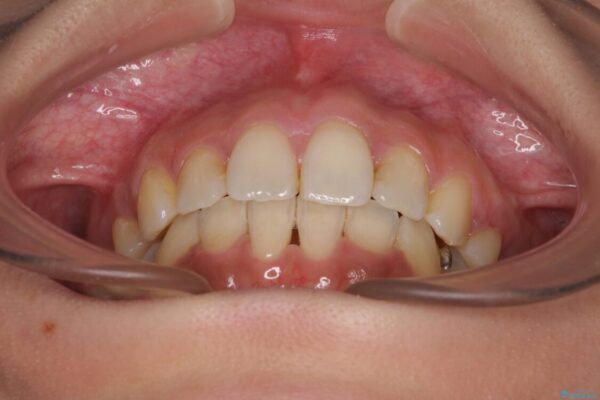

治療途中

• デコボコと口元の突出感 ハーフリンガルでの抜歯矯正 治療途中画像

前歯のデコボコと上顎の前突感による口の閉じにくさを気にして来院された患者様です。

目立たない装置を希望されたので、上顎が裏側装置のハーフリンガルを選択し、上下左右の小臼歯(計4歯)を抜歯して矯正治療を行うこととしました。